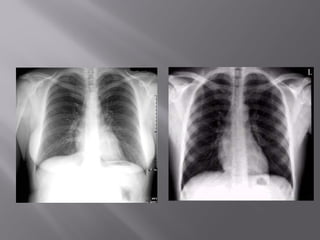

Pitfall Due to AngulationPitfall Due to Angulation

A film which is apical lordotic (beam is angled upA film which is apical lordotic (beam is angled up

toward head) will have an unusually shaped heart andtoward head) will have an unusually shaped heart and

the usually sharp border of the left hemidiaphragm willthe usually sharp border of the left hemidiaphragm will

be absentbe absent

Apical lordotic Same patient, not lordotic

Pitfall Due toAngulationPitfall Due to Angulation A film which is apical lordotic (beam is angled upA film which is apical lordotic (beam is angled up toward head) will have an unusually shaped heart andtoward head) will have an unusually shaped heart and the usually sharp border of the left hemidiaphragm willthe usually sharp border of the left hemidiaphragm will be absentbe absent Apical lordotic Same patient, not lordotic